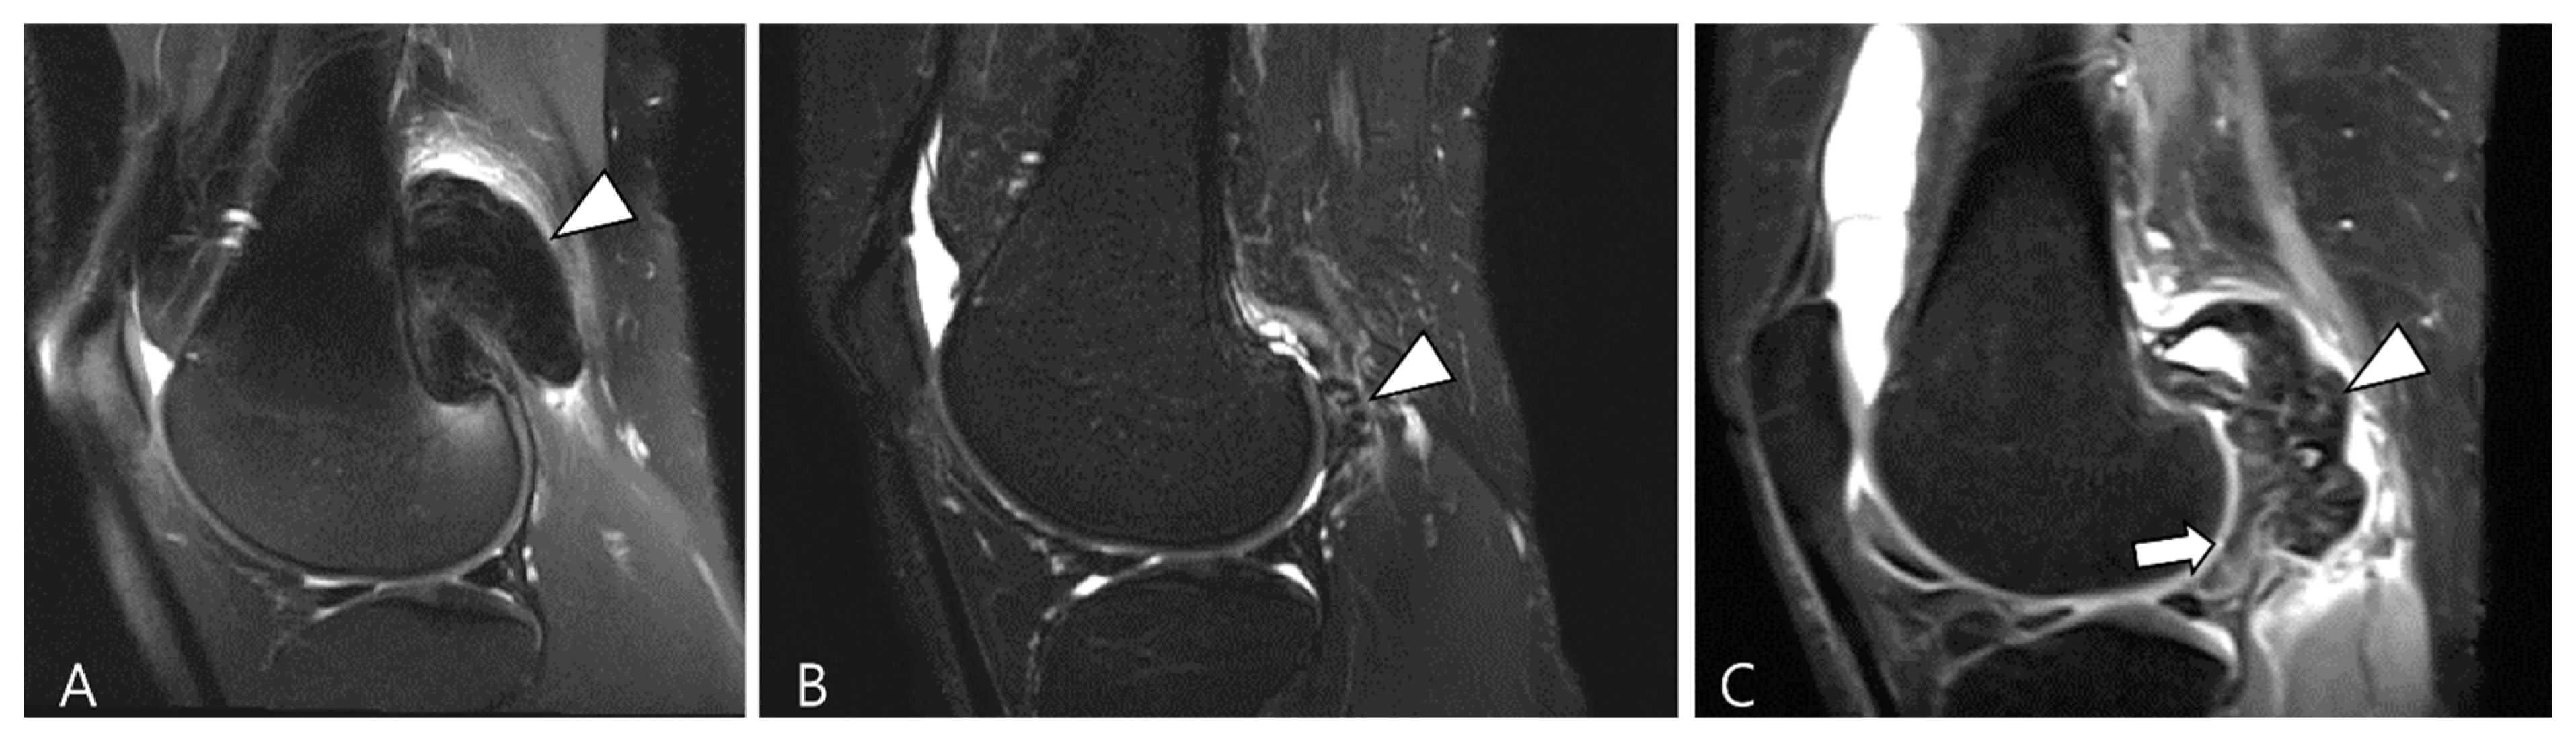

3.1. Differential Diagnoses of Intra-Articular D-TSGCT

3.1.1. Hemosiderotic Synovitis

3.1.2. Synovial Chondromatosis